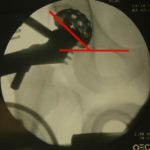

διευκολύνοντας το έργο του χειρουργού. Αποτελεί έναν επιπλέον “βοηθό” ο οποίος μάλιστα είναι απόλυτα ελεγχόμενος και απόλυτα σταθερός. Βοηθά την εφαρμογή δύναμης έλξης σταθερά και προβλέψιμα σε όποιο βήμα απαιτείται. Άλλο ένα σημαντικό πλεονέκτημα της πρόσθιας προσπέλασης, λόγω της θέσης του ασθενούς, είναι η δυνατότητα χρήσης ακτινοσκοπικού μηχανήματος (C- arm) καθ’όλη τη διάρκεια της επέμβασης. Με αυτόν τον τρόπο ο ορθοπαιδικός χειρουργός μπορεί να ελέγχει τα «βήματα» του κατά το οστικό σκέλος της επέμβασης αν κάποια στιγμή έχει αμφιβολία για αυτά. (εικόνα 13 ). Μπορεί να ελέγξει παραμέτρους όπως γωνία και βάθος τοποθέτησης των εμφυτευμάτων ή όπως το μήκος του σκέλους (μια παράμετρος σημαντική στην οποία συχνά δε δίδεται έμφαση, αν και η ανισοσκελία μετά την επέμβαση μπορεί να είναι ιδιαίτερα ενοχλητικό πρόβλημα!).